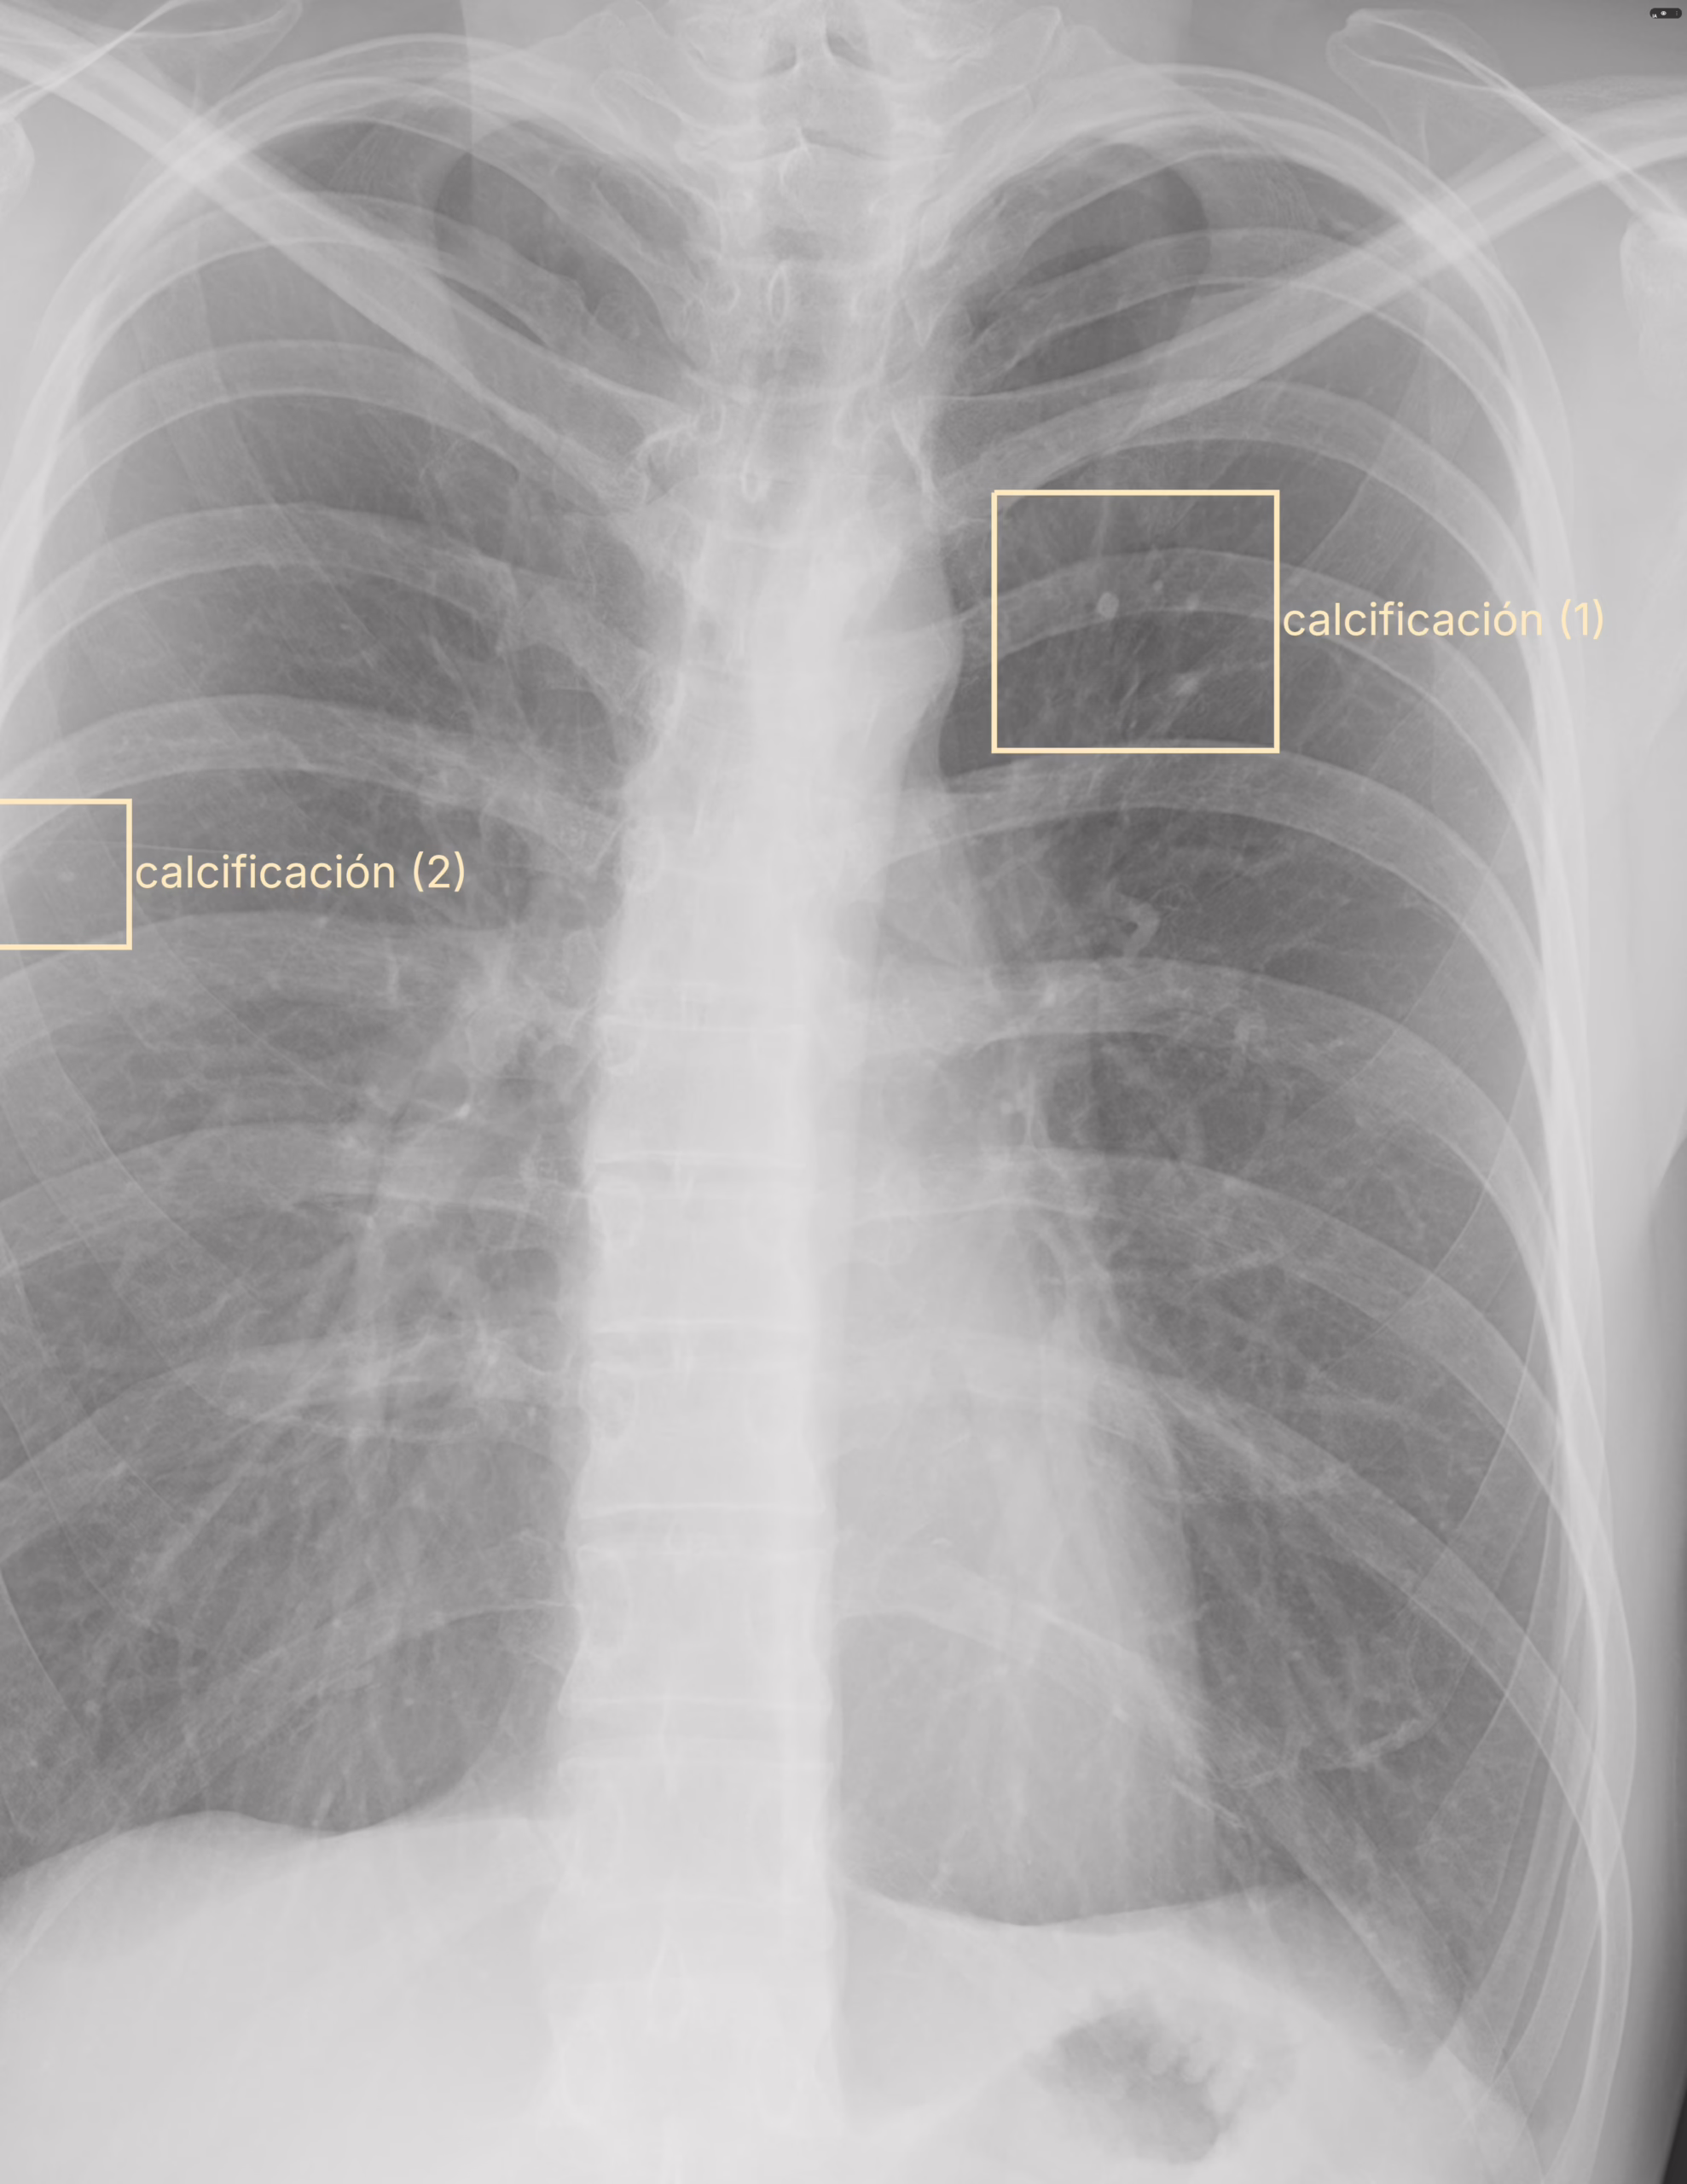

Los pulmones son simétricos y radiolucidos, de manera bilateral en los tercios medio se observa calcificaciones menores a 0.5 cm. No se identifican patrones radiopacos o radiolucidos por este método de estudio. El diafragma conserva la convexidad. Los ángulos diafragmáticos conservan la profundidad.La tráquea se encuentra central con presencia de aire. El arco aórtico se encuentra normal. La silueta cardiaca es homogénea.Los hilios son de diámetro normal y situación anatómica normal.

Calcificaciones pulmonares bilaterales